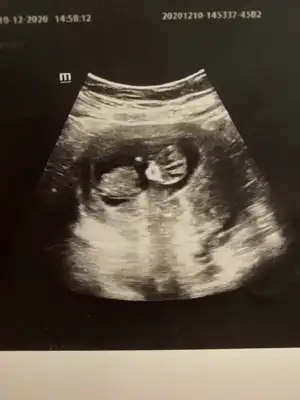

dr soylemeden siz gorun genital nub teorisi ( bebegin cinsiyeti)

Kızlar 12 haftalık yorum yapabilirmisiniz?

Ramzi teorisine göre erkek gözüküyo ama oda kesin çıkmıyo tabi. İlk bebeğinizmi

Erkek ve kız için 11 + 12+ yada 13 hafta usg görüntüsü olmalı açıklamalar asagıda yazıyor 😊 rabbim herkesin gönlüne göre nasip etsin inşallah .. ecmain

[/B]Eki Görüntüle 473828 gordugunuz gibi ust taraftaki simgedende anlasildigi gibi eger cikinti paralel ise kiz

yok 30°lik bir aciyla yukari dogru bakiyorsa %99 oglunuz olacak demektir simdi bi kac ornek resimler daha koyacagim kiziminkide dahil

Eki Görüntüle 473829 bu bir erkek bebek genital nub cikintisi gayet yukarda

Eki Görüntüle 473831 simdi burada cikintilara bakin eger bel popo cizgisine paralel ise kiz

yok 30 derecelik bir aciyla yukari bakiyorsa erkek

yabancilarin hepsi biliyor bunu biz neden eksik kalalim gayet bilimsel simdi ellerinde11 12 13 ultrason fotografi olanlar alsin hemen baksin yada koyalim buraya yorumlayalim

hani dr lar 12. 13. haftalarda belli degil ama

kemik yapisina gore kiz gibi

yahut erkege benziyor diyorlar ya

iste o nub teorisi kizlar dr buradan yola cikiyor